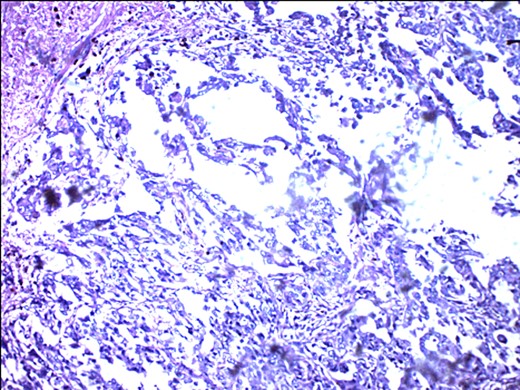

Metastasizing glandular component of MBC, melanocytic variant, with few pigment deposits.

ER negativity for rabbit monoclonal antibodies. Few stromal cells are positive black.